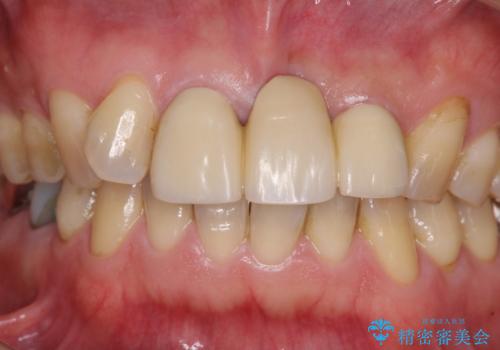

- 保険診療の前歯のブリッジが、形態も色も不自然で気になるとのことで来院された患者様です。

神経の抜かれている土台の歯は根管治療を行った上で、オールセラミックブリッジにより補綴することとしました。

術前の状態より、欠損部位には歯肉移植術が必要と思われましたが、仮歯で調整したところ自然な歯列となったため、外科処置は行わずに自然な口元に仕上がりました。